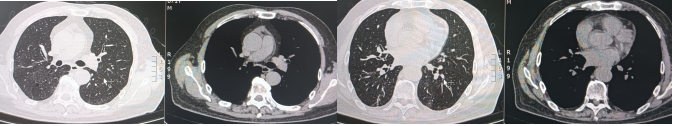

入院后给予奈诺沙星0.5 g qd ivgtt、头孢他啶阿维巴坦2.5 g q8h ivgtt经验性抗感染治疗。治疗5天后复查相关指标:白细胞计数9.69×109/L,中性粒细胞绝对数7.31×109/L,C反应蛋白90.4 mg/ml,血清淀粉样蛋白>288.00 mg/L,红细胞沉降率测定94 mm/h;胸部CT:右肺上叶、下叶间质性炎症,左下肺小结节,炎性结节可能(图2)。提示病变无明显好转,告知家属病情后再次行气管镜检查,行病原学检查及病理检查,结果示:BALF涂片、培养、GM均阴性;BALF NGS回报:流感嗜血杆菌、烟曲霉。冷冻肺活检病理:(右肺下叶后基底段)肺组织急、慢性炎,肺泡腔内见纤维素样渗出物伴泡沫细胞聚集。免疫组化结果:CK7(+),TTF1(+),SMA(平滑肌+),NapsinA(+),PGM-1(+),Ki-67(+, 5%),P40(+),CD68(+)。考虑真菌感染不除外于8月31日加用伏立康唑0.2 g q12h ivgtt;醋酸卡泊芬净70 mg qd ivgtt抗真菌对症治疗。图2 2024年8月27日复查胸部CT较8月21日胸部CT无明显吸收9月5日再次复查相关指标:白细胞计数12.38×109/L,中性粒细胞绝对数9.27×109/L,C反应蛋白151.46 mg/ml,血清淀粉样蛋白>288.00 mg/L,红细胞沉降率117 mm/h。胸部CT:右肺散在间质性炎症,左下肺新发炎症灶,较前进展,左下肺小结节,范围较前增大(图3)。图3 2024年9月5日胸部CT右下肺炎症较8月27日进展,左肺出现新发炎症灶9月5日行MDT讨论,考虑感染继发机化性肺炎不除外,建议在目前抗感染治疗保驾下予中等剂量激素治疗,并严密动态观察相关指标。9月6日起治疗上加用甲泼尼龙琥珀酸钠80 mg qd ivgtt。治疗1周后(9月12日)复查相关指标:复查炎症标志物:白细胞计数16.47×109/L,中性粒细胞绝对数14.79×109/L,C反应蛋白11.08 mg/ml,血清淀粉样蛋白25.388 mg/L,红细胞沉降率28 mm/h。胸部CT:双肺散在间质性炎症(右肺为著),较前吸收(图4)。9月12日调整激素剂量为醋酸泼尼松片35 mg qd口服;9月19日患者无发热,无明显咳嗽、咳痰不适,予出院并嘱出院后维持醋酸泼尼松片35 mg qd口服,1周后每周减5 mg,减至20 mg后维持1周并复查胸部CT,根据胸部CT结果调整剂量。10月21日患者门诊复查胸部(图5),较前明显吸收,激素调整为醋酸泼尼松片10 mg qd,目前在持续随访中。治疗期间感染相关指标变化情况如图6所示。机化性肺炎(organizing pneumonia,OP)是一种肺组织修复过程,是以肺泡腔/管内有息肉状肉芽组织为病理特点,主要由成纤维细胞、肌成纤维细胞和疏松结缔组织基质构成[1]。同时与其他肺损害,如血管炎、淋巴瘤、肺癌、过敏性肺炎(hypersensitivity pneumonitis,HP)、嗜酸性粒细胞性肺炎(eosinophilic pneumonia,EP)、急性间质性肺炎(acute interstitial pneumonia,AIP)、非特异性间质性肺炎(nonspecific interstitial pneumonia,NSIP)或普通型间质性肺炎(usual interstitial pneumonia,UIP)关系密切。OP具有复杂的多态性,具有急性、亚急性和慢性多种形式。OP可以根据病因分为隐源性机化性肺炎(cryptogenic organizing pneumonia,COP)和继发性机化性肺炎(secondary organizing pneumonia,SOP)。COP与SOP在临床表现、影像表现和肺功能无明显差异[2],当有相关病因时诊断为SOP,当临床未发现相关潜在疾病时诊断为COP。OP的概念最早在肺炎链球菌的大叶性肺炎中被阐述,OP的发病机制目前主要认为肺泡上皮损伤,纤维蛋白渗出,导致成纤维细胞增生-肌成纤维细胞增生[3]。机化存在于多种肺损伤中,具有相同的本质,无论是局灶性还是弥漫性肺损伤,以成纤维细胞增殖为特征的机化是一种常见且几乎普遍的反应[4],机化被认为是对炎症渗出的反应和局限,很可能代表疾病的一个阶段,而不是独立的疾病。所以如果有确认感染的证据,虽然CT上发现有机化的特征,临床诊断OP往往是不必要的,除非这种机化是主要表现,而且改变了疾病进程。因此关注整体,将OP作为疾病的一个阶段,有利于建立对疾病的全息认识。OP没有特异的临床特征,患者可能出现发热、咳嗽、乏力、轻度呼吸困难、厌食症和体重减轻等,类似于流感[5],临床表现不特异。有些患者接受经验性抗生素治疗后往往无效,且疾病可能会迅速进展,导致严重的呼吸困难,甚至是ARDS,往往存在延误诊断。有文献报道大部分OP患者为不吸烟患者,肺功能主要表现为限制性通气障碍,也可表现为混合型和阻塞性通气障碍[6]。也有学者研究SOP患者有胸腔积液,而COP患者未报告胸腔积液[7]。因此,胸腔积液似乎与背景疾病有关,而与OP本身无关。OP的CT表现可以按照发生率分为典型和非典型模式[6],多数患者表现为典型模式,即多灶性实变,常被描述为斑片状肺泡阴影,一般位于下肺外周或支气管血管周围;实变可伴有支气管充气征,并可伴有散在的磨玻璃病变或小结节。而非典型的病变表现多样,可为磨玻璃影,也可为结节或肿块样表现、反晕征、铺路石征、小叶周围病变、线性和带状阴影以及网状结构。OP虽然有多种影像学表现,但均不特异,类似的表现同样可以出现在其他疾病中。例如,迁移性病灶可提示嗜酸性粒细胞性肺炎、感染、血管炎和复发性出血[8];弥漫性微小结节可见于过敏性肺炎、细支气管感染和炎症;反晕征可见于多种感染、非感染性肉芽肿异常,甚至原位腺癌[9]。因此诊断OP不能单纯依靠CT,需要结合临床和病理特征。目前针对OP的治疗,COP主要是以糖皮质激素为主[10],SOP需要兼顾原发疾病治疗及激素应用,因此我们需要尽早明确病理,及时治疗,减少不良预后。针对重症患者,尽早获取病理是必要的。此病例我们初步诊断为CAP,予抗感染治疗后疾病进展,及时行二次支气管镜冷冻肺活检+灌洗,同时通过mNGS及病理检查,最终被诊断为SOP,经激素抗炎治疗后症状好转,影像学提示病灶明显吸收。总之,OP在临床上并不少见,但由于其临床表现无特异性且CT表现多样,所以及时正确诊断OP罕见,诊断OP需要结合临床和病理特征,只有当OP成为主导性特征且干扰了疾病进程,才被冠以OP的诊断。针对初诊为肺炎的患者,当经验性抗感染治疗效果欠佳时,需要及时明确病原学检查及病理诊断,及时修改诊断及治疗路径,及时干预[11]。[1] CottinV,CordierJF. Cryptogenic organizing pneumonia[J]. Semin Respir Crit Care Med, 2012, 33(5): 462-475.